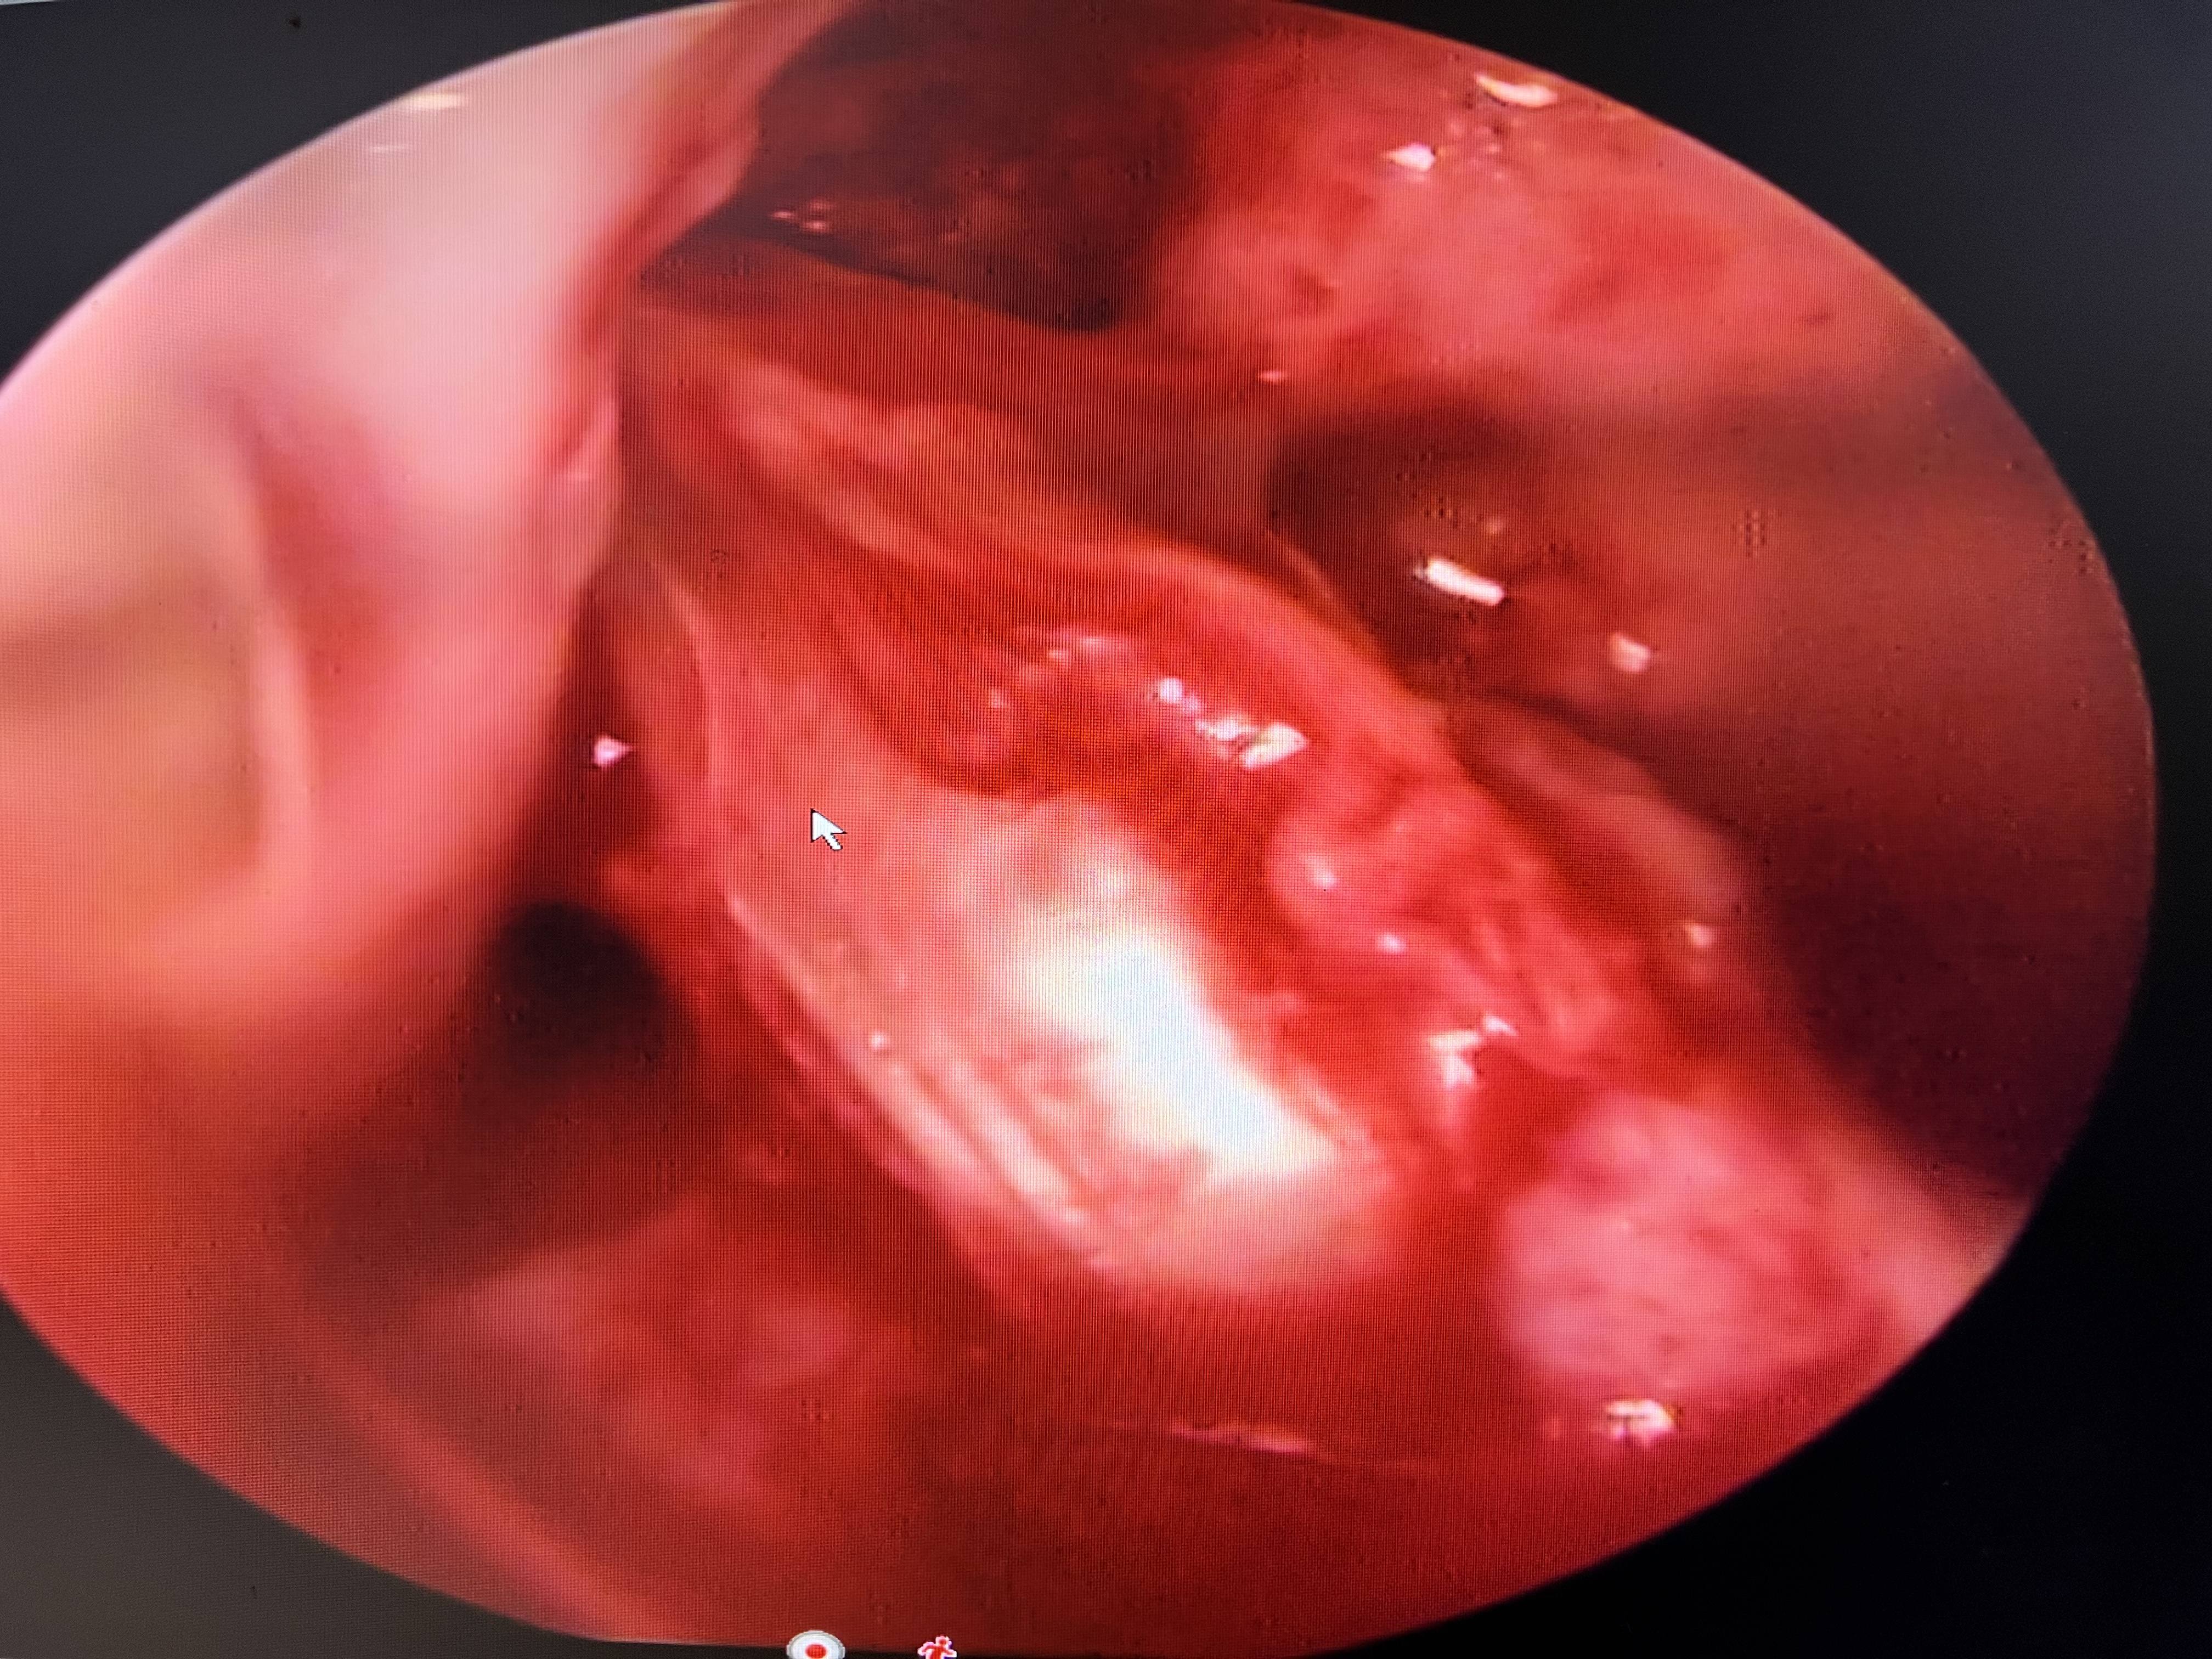

ACL ligament ka best treatment kya hota hai ?

ACL ligament me yadi grade 3 tear ho to apne aap sahee nahee hota, iske liye durbeen se surgery karna padta hai . bahut se log dr naveen ke [paas iske treatment ke liye ate hhai.